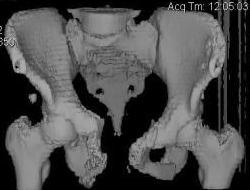

Уважаемые коллеги! Девушка 18л сросшиеся переломы лонных, седалищных костей с обеих сторон, перелом крестца справа,перелом костей голени справа (зио), 3 мес после травмы, АВФ снят с таза. Патологической подвижности нет. Стоит самостоятельно, ходит с костылями, поскольку 3 месяца практически не ходила. Беспокоит выступание лонной кости в области лобка, хотя объективно грубого косметического дефекта нет. На кт разворот лонной кости в сагиттальную плоскость. Вопрос: стоит ли добиватьсяполной репозиции или же достаточно произвести остеотомию верхушки выступающего отломка?

Предварительный диагноз- посттравматическая вертикальная нестабильная деформация таза II степени, неправильно срастающийся перелом боковой

массы крестца справа, правой лонной и седалищной костей, застарелый разрыв лонного сочленения.

Для уточнения диагноза ниеобходимы обзорные рентгенограммы таза (прямая и inlet), Кт срезы на уровне переломов для определения степени сращения и решения вопроса о методе оперативного восстановления анатомии (делать ли остеотомию, низводить ли задние отделы), ни о какой "остеотомии выступающих отломков" тем более у девочки 18 лет речи быть не может.